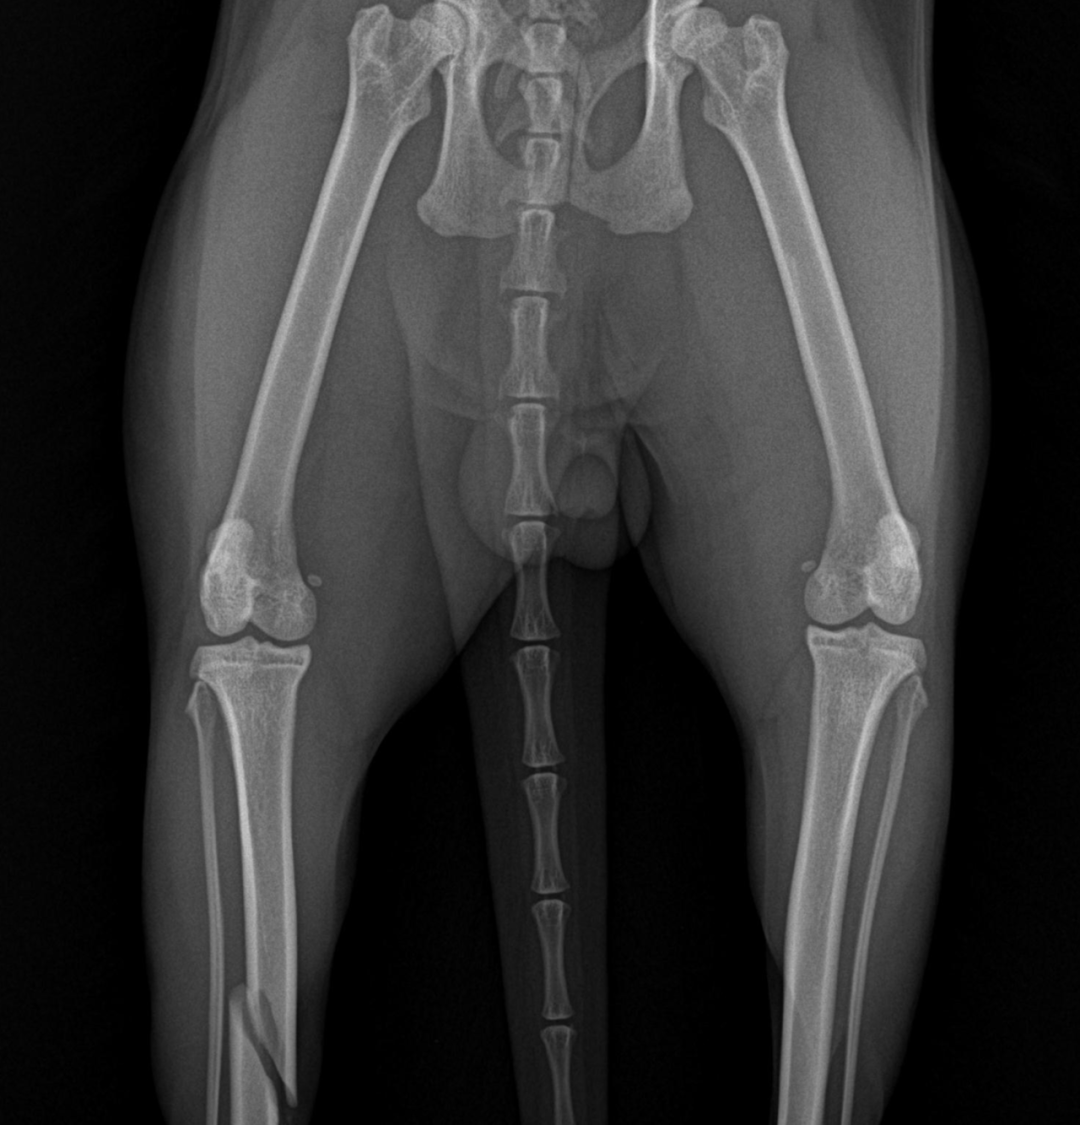

当晚,光挂号和拍X光片就花了409元,“150元/张,正面侧面都得拍”。对着片子,医生诊断核桃确实骨折了,随后报出了1.2万元的治疗价格。

图 | 当时拍的片